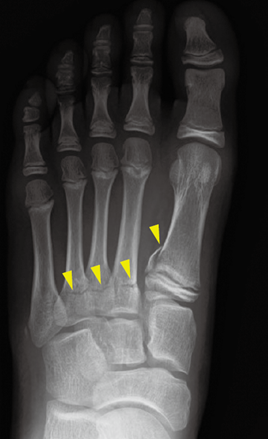

中足骨基部骨折について

黄色矢印部分に骨折線が認められています。

(図20) MB Orthop. 38(5):55—64,2025大人とこどものスポーツ外来 下肢編【こども編】小児アスリートの足関節・足部捻挫に対する外来診療 田中 博史 より抜粋